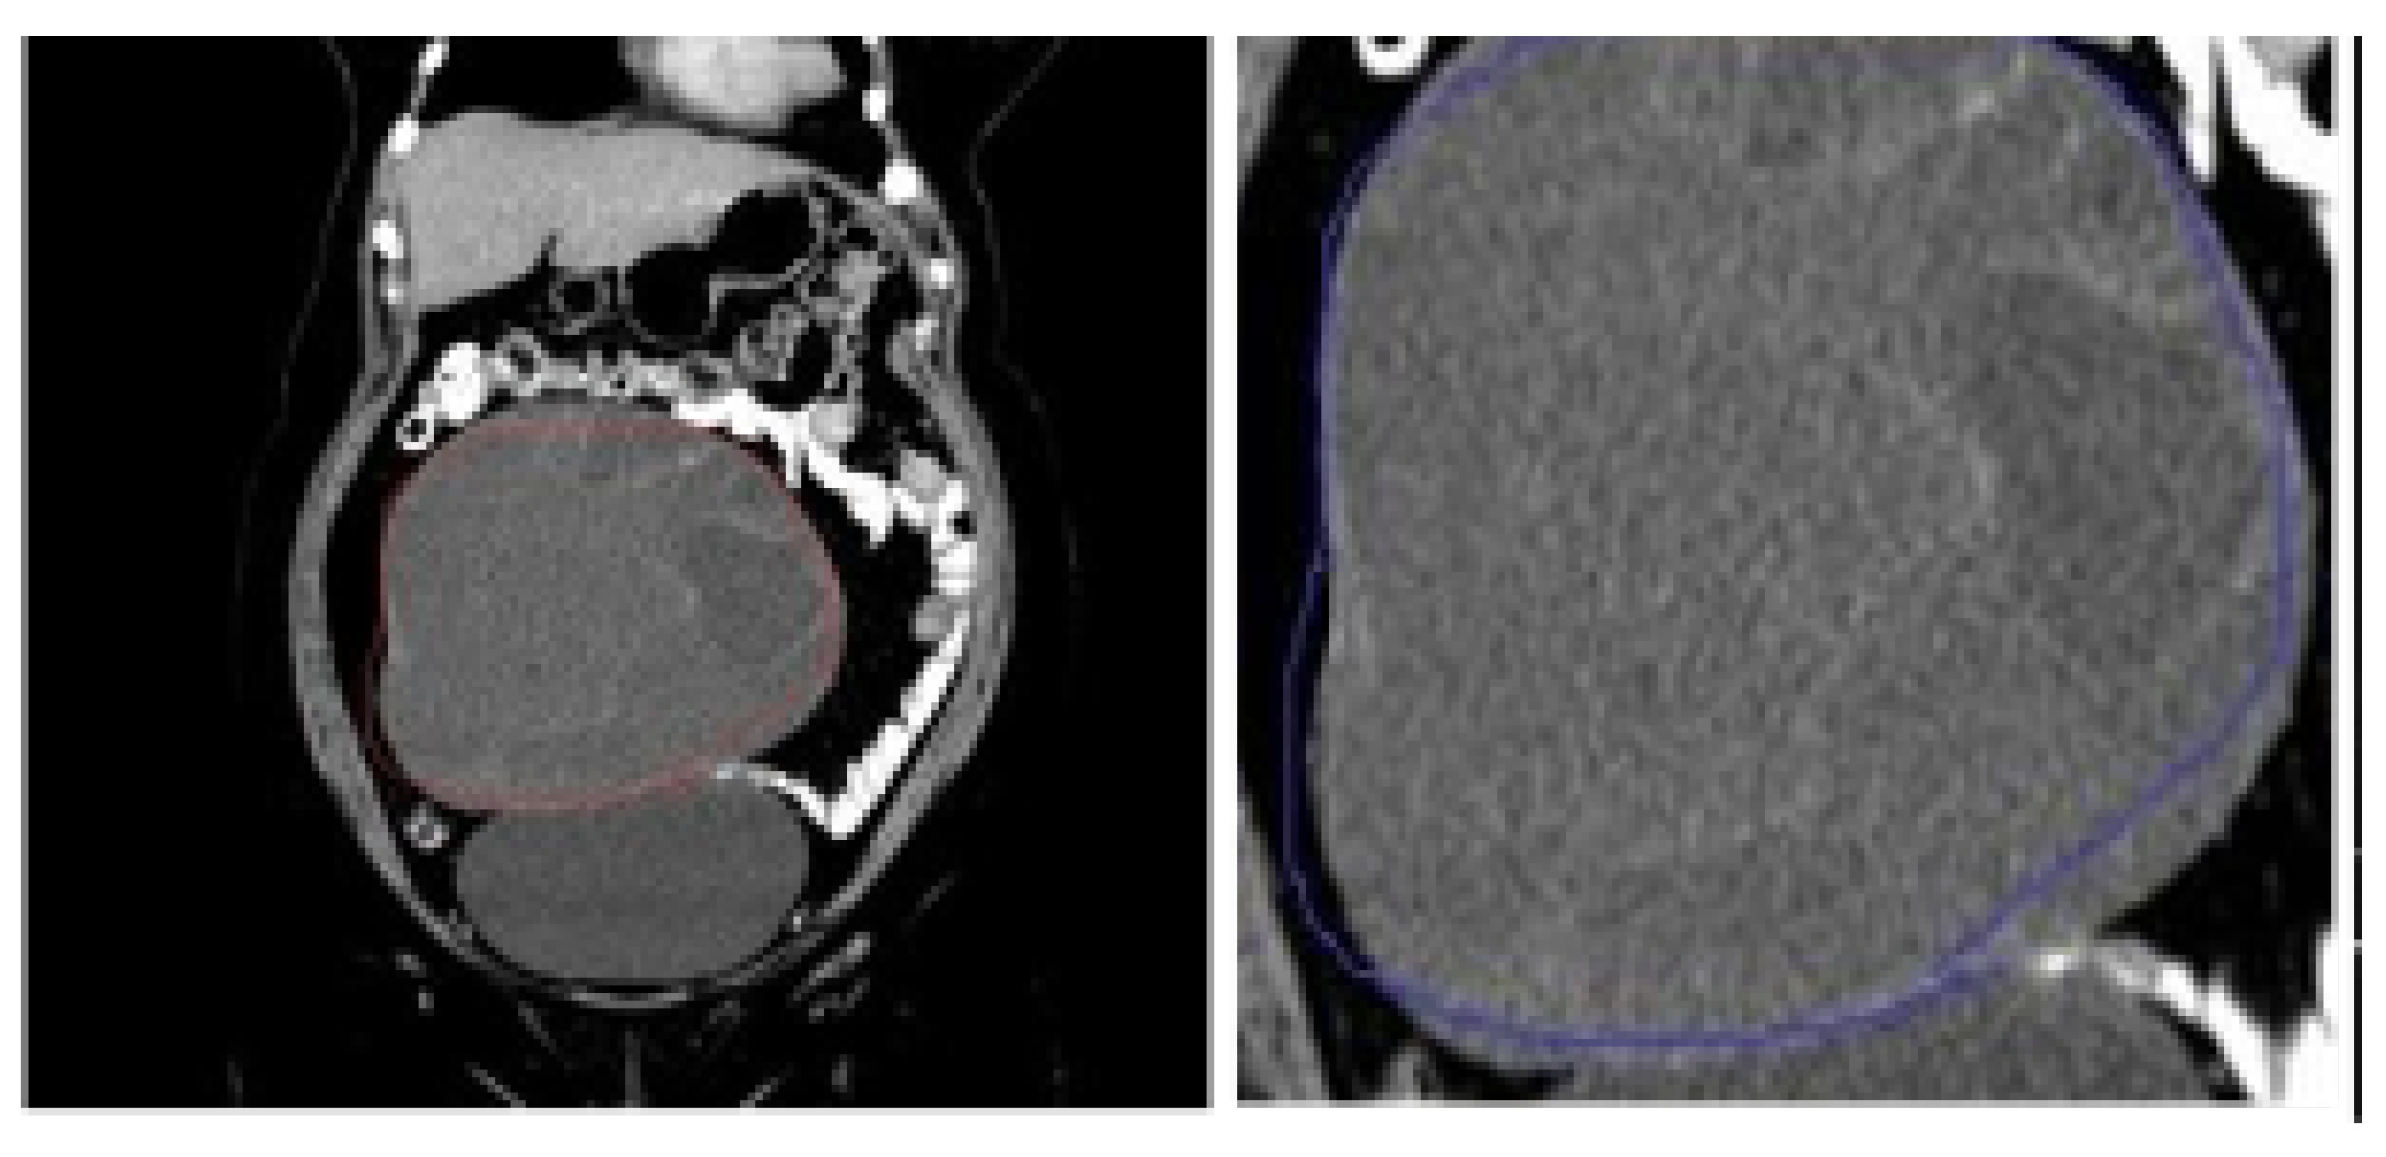

5.1. Data Source and Description

5.2. Data Preprocessing and Dataset Preparation for Training and Evaluation